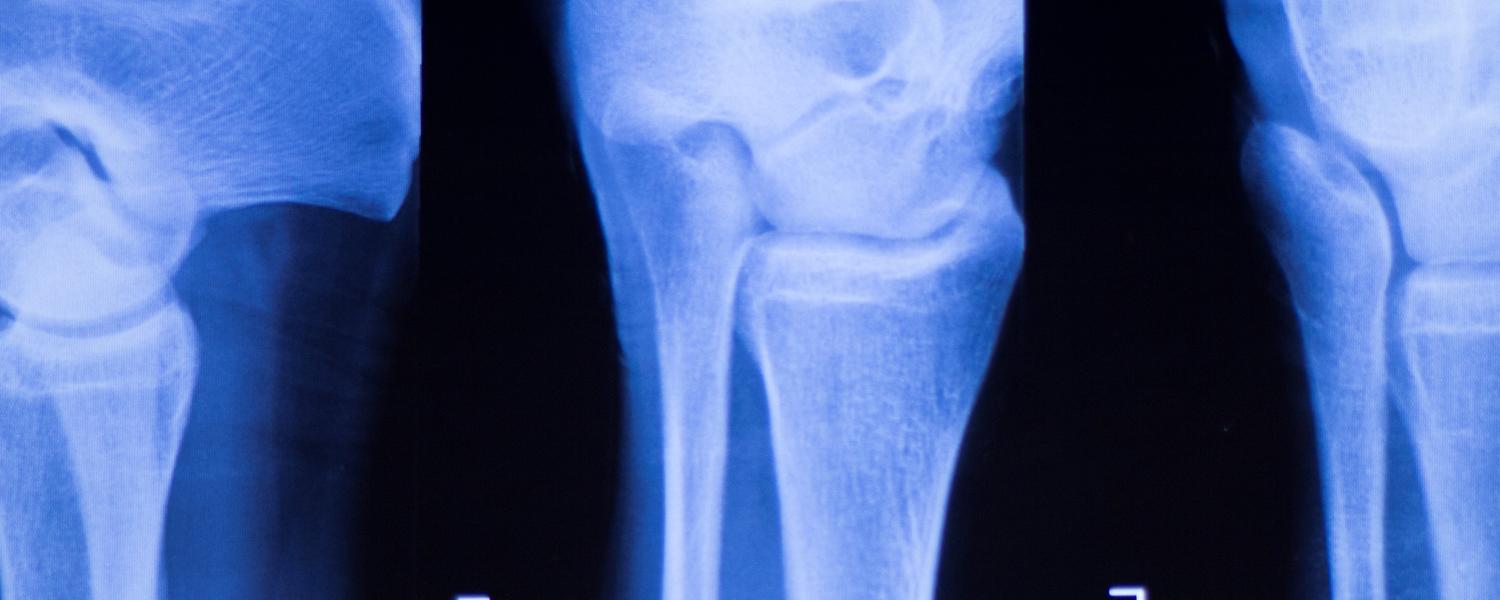

Understanding the biomechanics of the joint

“I was always intrigued as to why and how things worked – from a very early age,” says McCaig Institute researcher Nigel Shrive. His curiosity, along with some sage advice from a teacher, led him to a degree in biomedical engineering, where he became interested in how joints function and what cases them to deteriorate in osteoarthritis (OA).

Shrive and his team study the mechanical and biological interactions that occur in joint or tissue after injury. These interactions affect the way loads get transmitted from one bone to another across a joint. Once researchers understand what causes the progression of OA, new ways to test for and treat the disease can be developed.